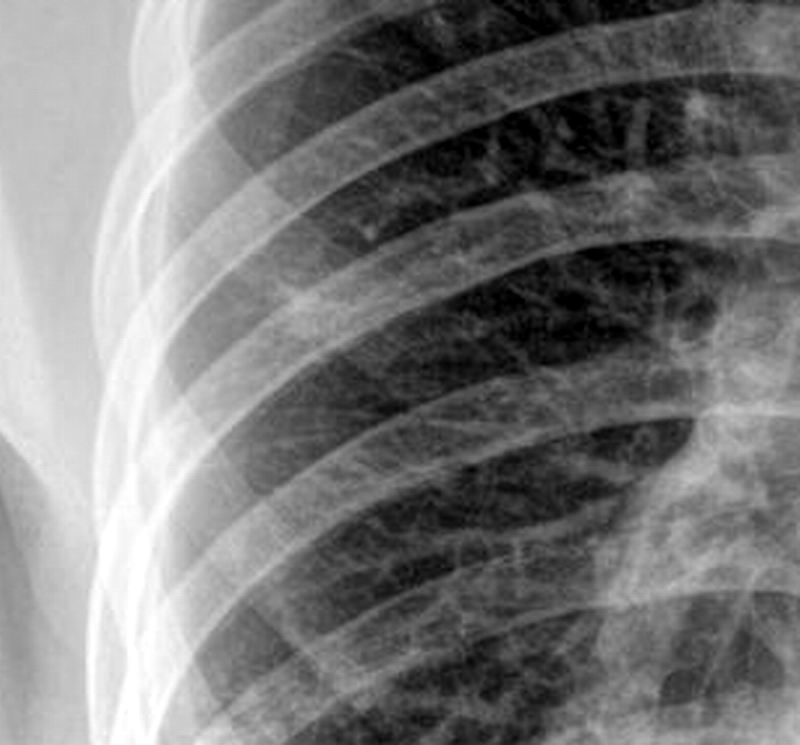

以下是引用zhanggenliang在2010-5-12 16:49:00的发言:[br]右肺的高密度影应该是中叶吧。请问治疗过程。是抽水呢?还是抗结核治疗,还是抗炎。如果抽水应该化验,因为化验鉴别明了,如果抗结核就不用说了。如果是考大家,只能说影像较支持结核